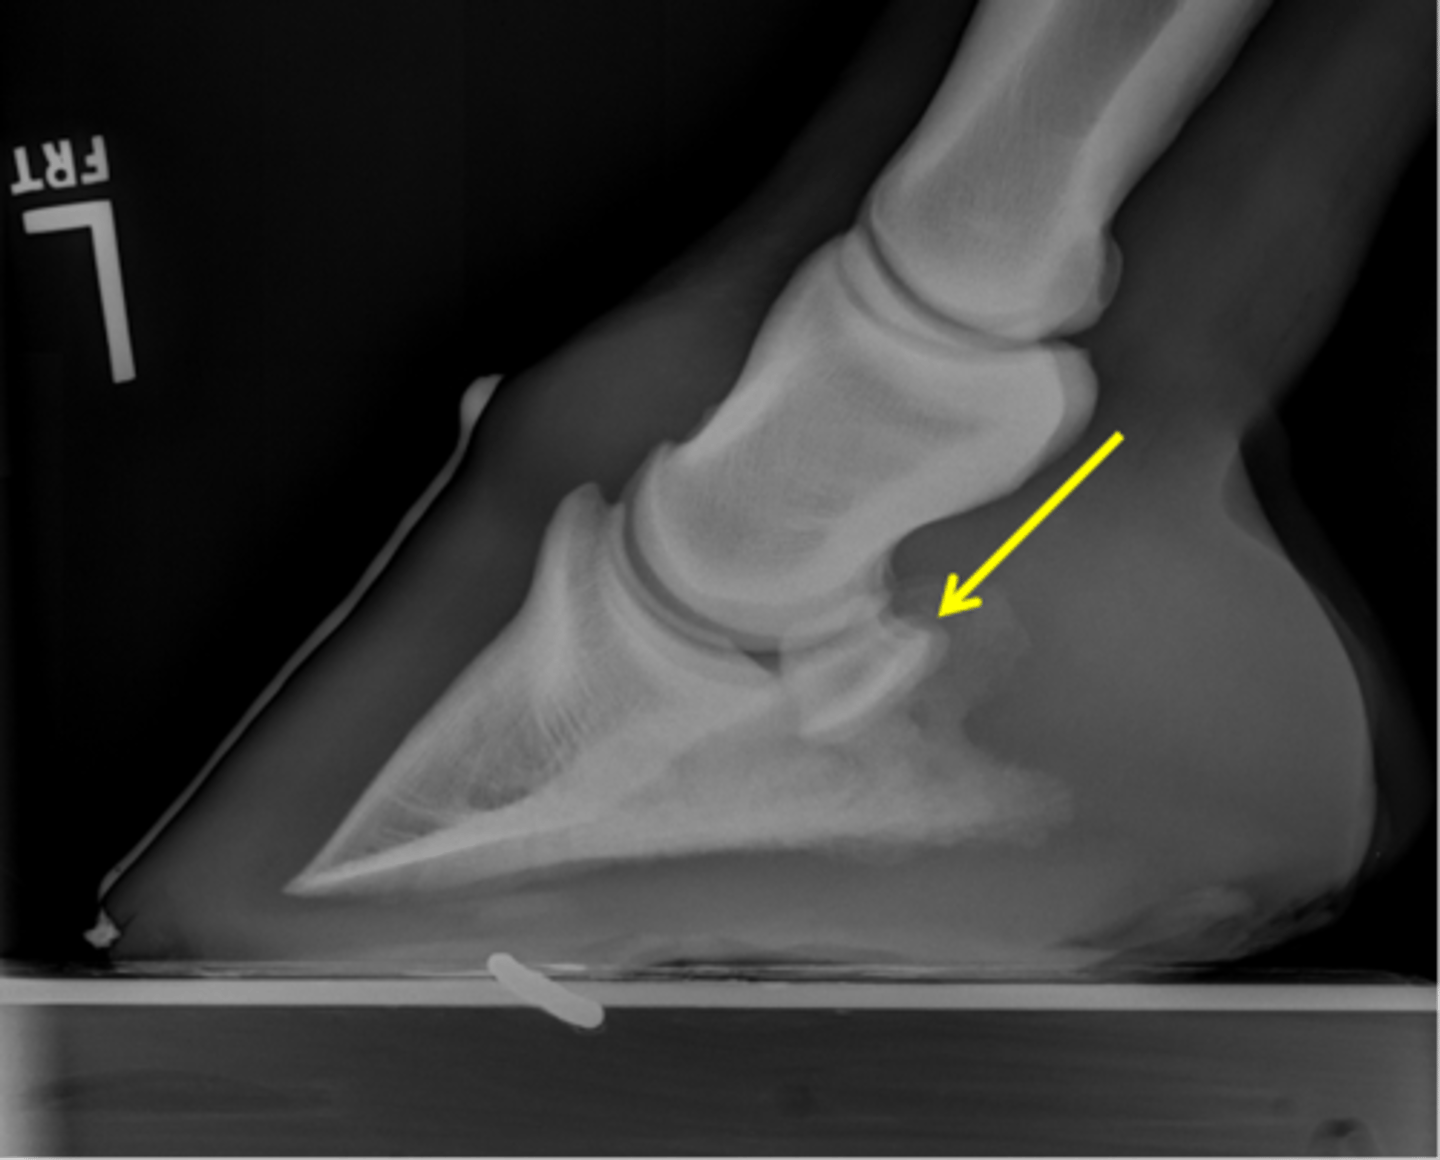

Coffin bone (P3)

Palmar process of P3

Extensor process of P3

Navicular bone

Coffin joint

Short pastern (P2)

Coffin bone

Navicular bone

Crena

Vascular channelsv

Solar canal